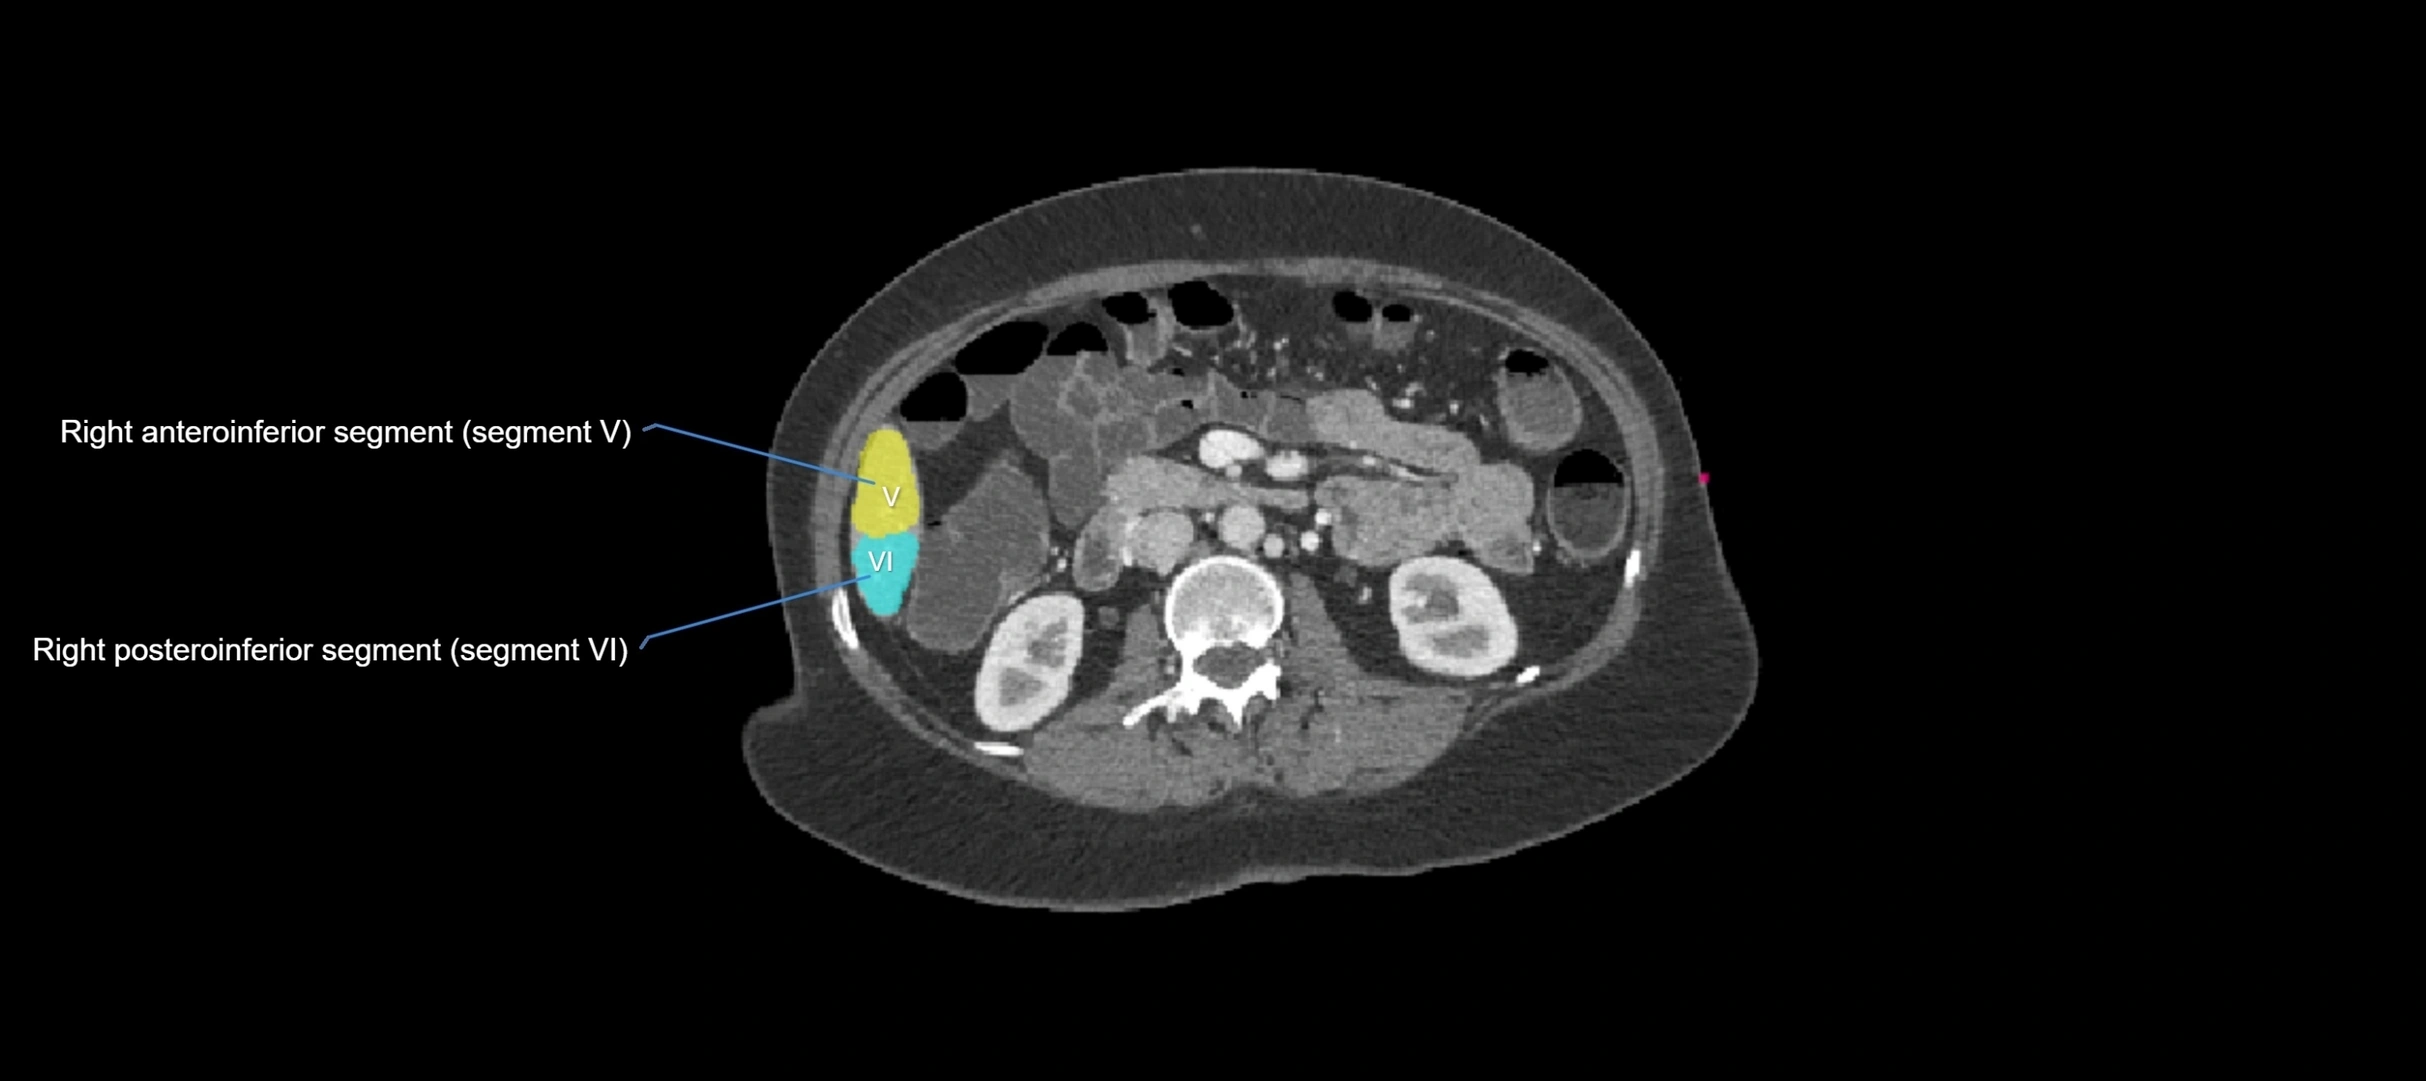

CT Appearance

CT Pre-Contrast:

• Caudate lobe appears as a soft-tissue density, isodense to the rest of the liver

• Enlargement may be appreciated in cirrhosis or Budd–Chiari syndrome

CT Post-Contrast:

• Homogeneous enhancement in the portal venous phase, similar to rest of liver

• Independent venous drainage into the IVC may be visualized

• Lesions follow characteristic CT enhancement patterns (HCC: arterial hyperenhancement with washout; hemangiomas: peripheral nodular enhancement with centripetal fill-in)

CT Venous Phase (functional significance):

• Caudate lobe often enhances relatively more than other lobes in Budd–Chiari syndrome, due to preserved venous outflow